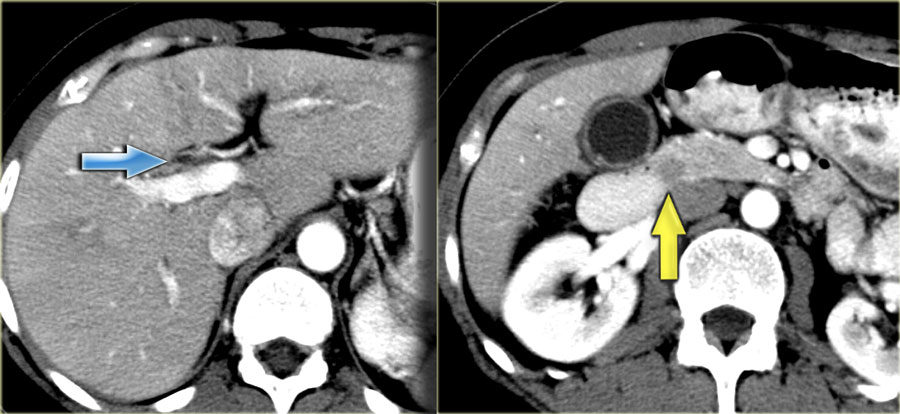

Абсцесс печени кт